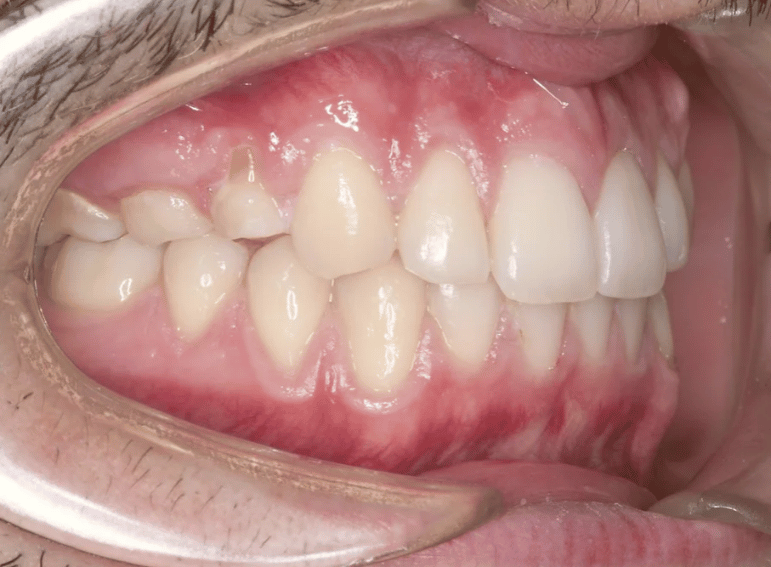

Replacement of retained primary teeth in a patient with hypodontia.